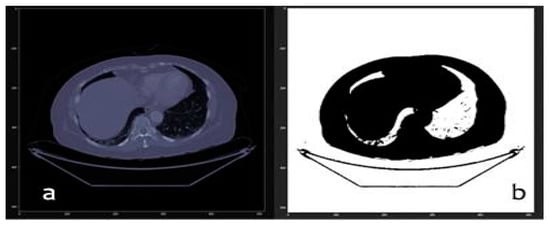

2.3. Computer Vision Algorithms

- Processed by thresholding: based on keeping the voxels whose intensities are within a fixed range, and setting the rest to a fixed value that is interpreted as the background of the image. This process is useful for separating structures when no different regions with similar intensities exist.

3.1. From dicom to 3D Models with Automatic Segmentation